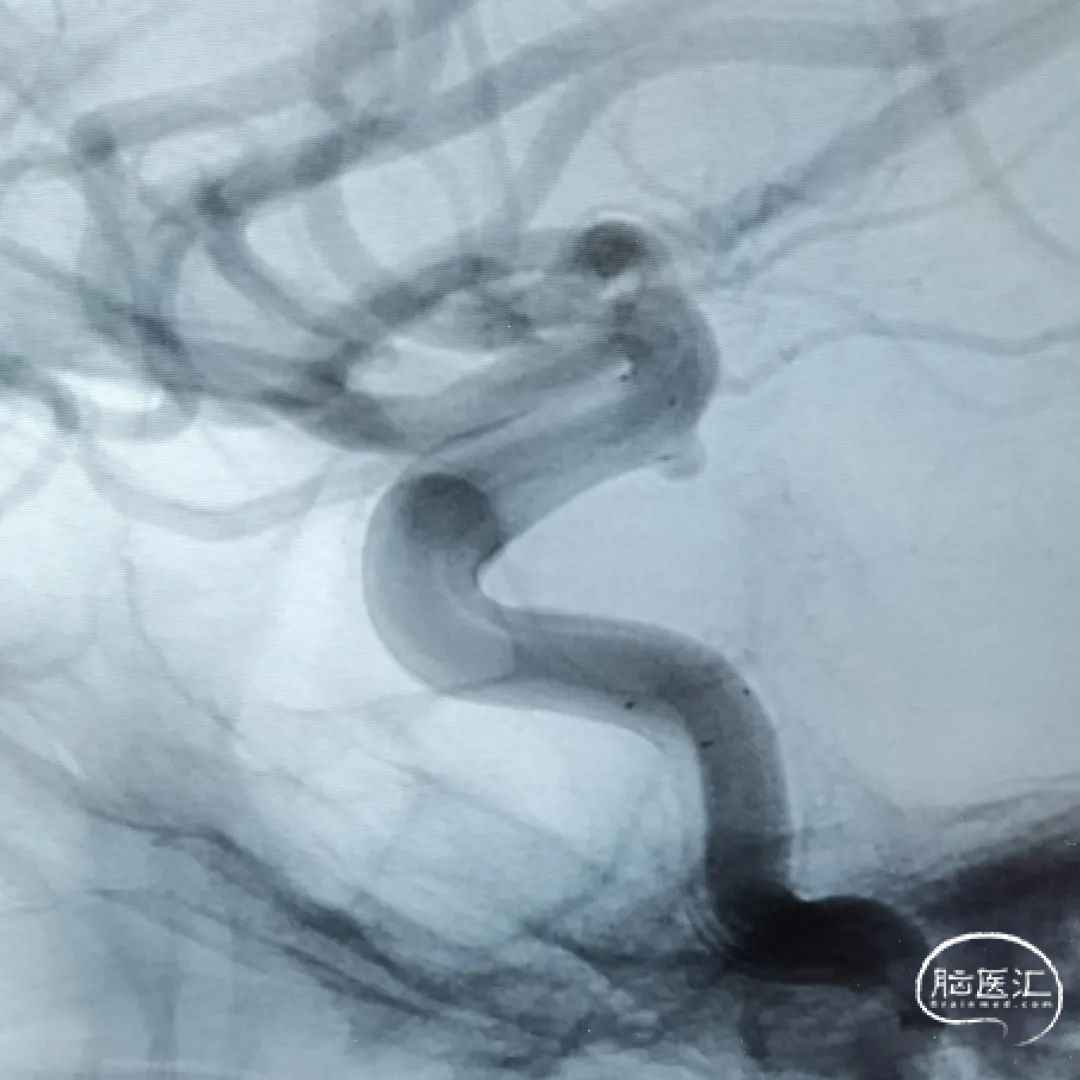

这是一根115cm 通桥银蛇®颅内支持导管,通过R-DAS技术非常容易地放置到海绵窦段,手术过程中实际到达了海绵窦段后膝的位置,在这样的情况下释放血流导向装置就非常容易。

6F 115cm 通桥银蛇®颅内支持导管 。

FD